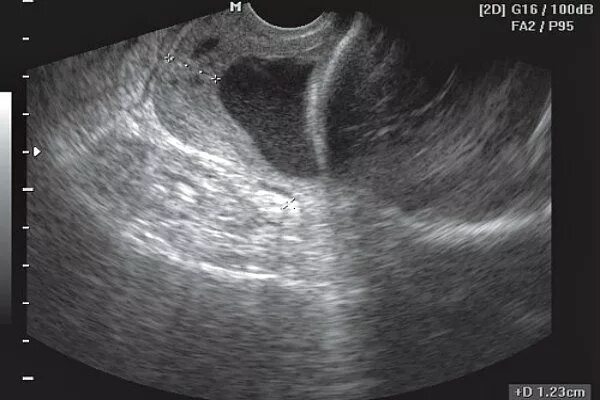

Расширение внутреннего зева при беременности